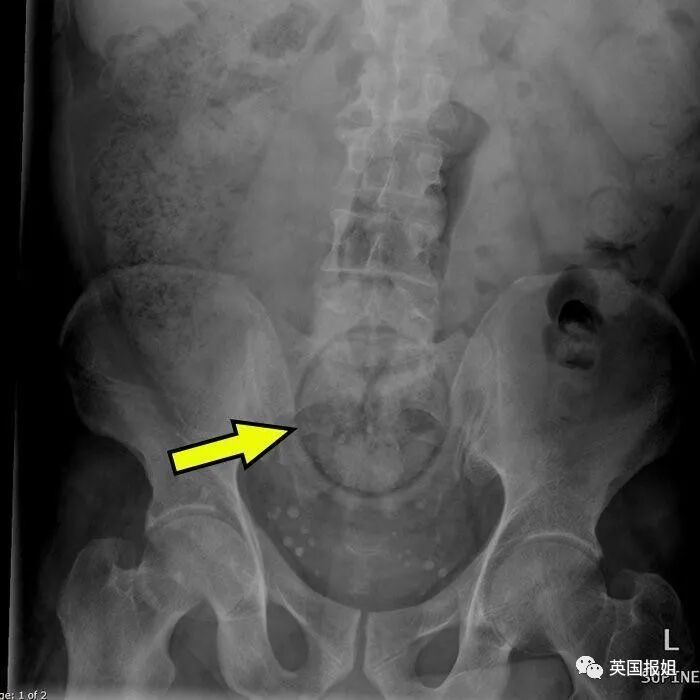

上个月,巴西某监狱一位男性囚犯肛门中被发现有8部带电的手机,4根USB线,7个手机芯片还有1根充电器电线…

他当时是刚到达监狱,接受电子检查,体内的电子装置直接被扫描仪显示出来了。